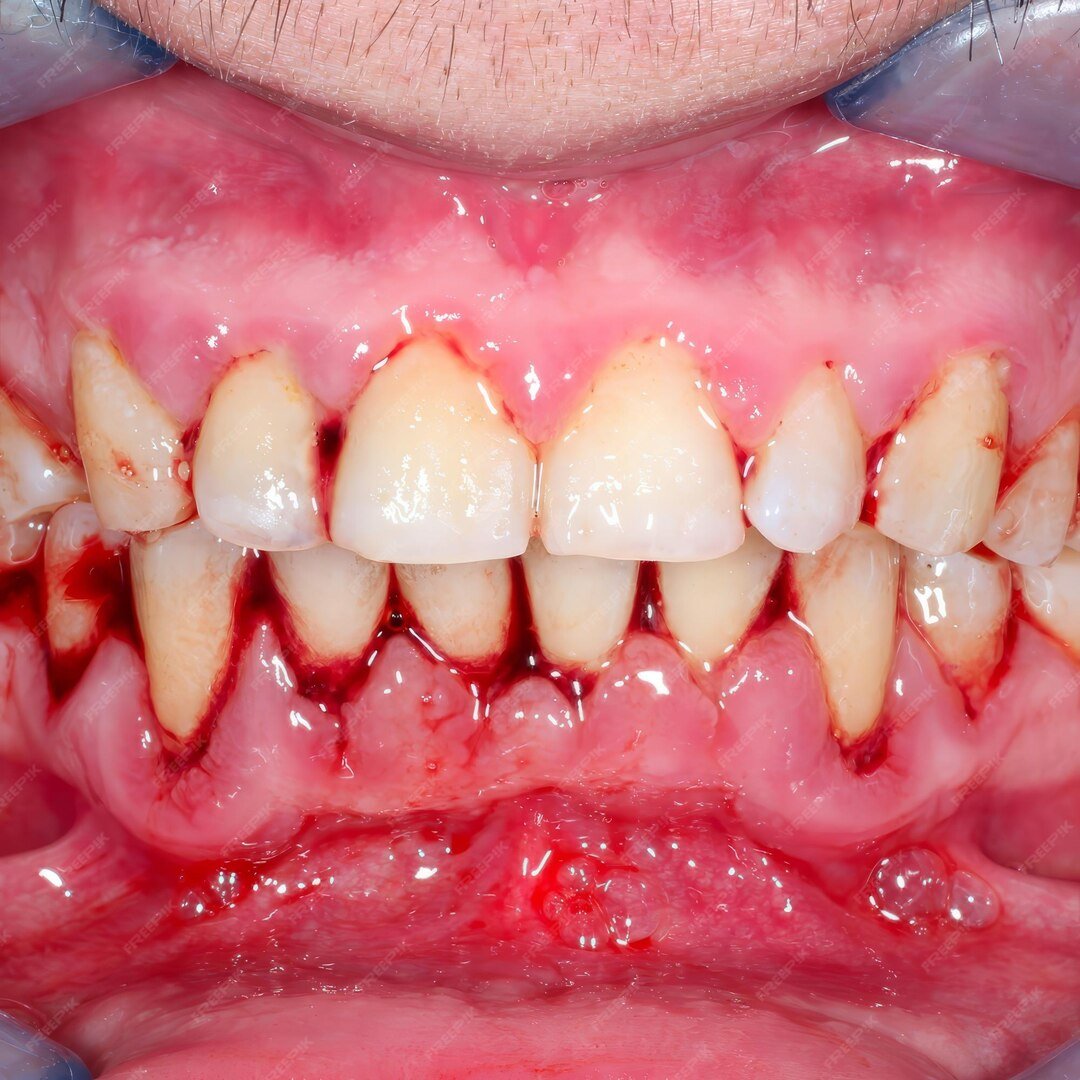

Gum surgery, also known as periodontal surgery, is a dental procedure that treats severe gum disease and restores the health of your gums and supporting bone. It is usually recommended when non-surgical treatments like scaling and root planing are not enough to stop infection.